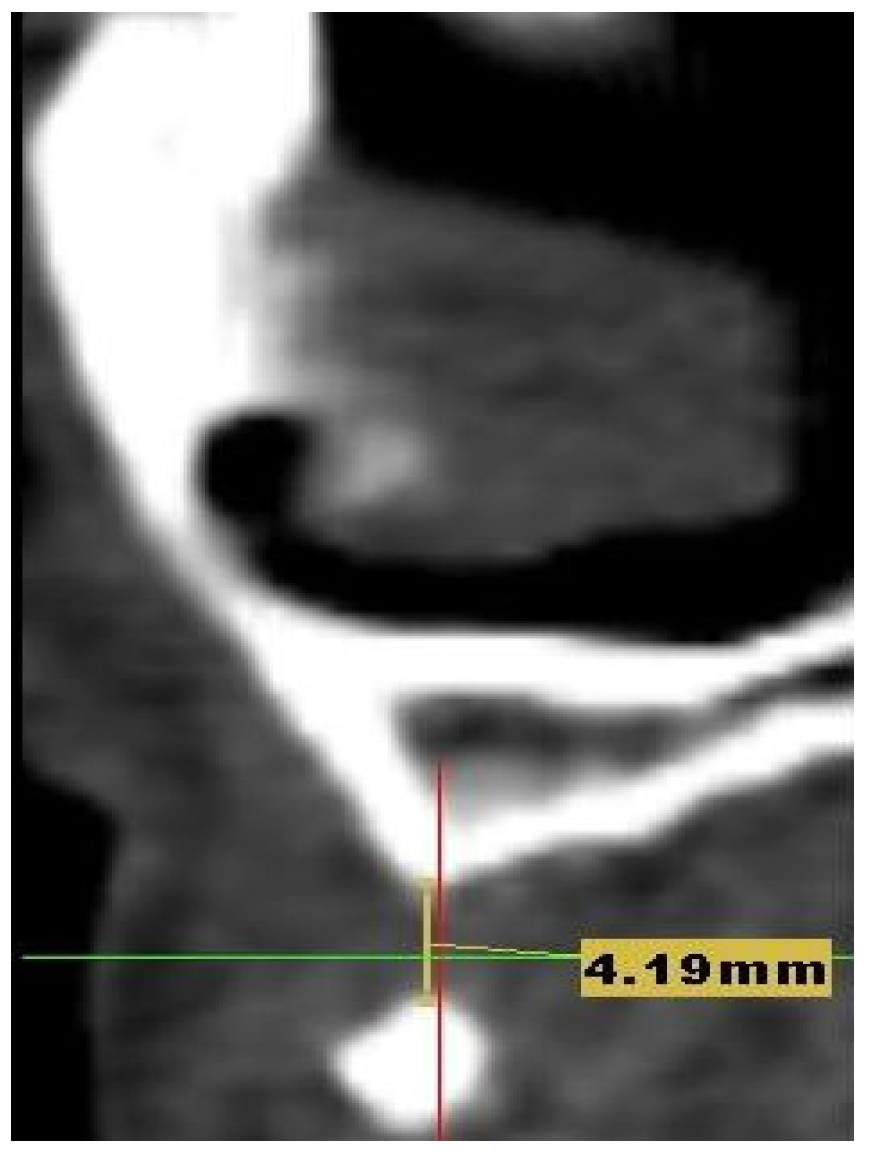

A 27-year-old woman presented to the dental clinic for aesthetic and masticatory dysfunction after a difficult odontectomy ten years ago. The provisional removable acrylic appliance (flipper) unsatisfied her and created a social disadvantage for the young woman. After a complete intraoral and extraoral examination (Figure 1A,B) and a cone-beam computerized tomography (CBCT) evaluation (Figure 2), the missing teeth 1.3, 1.2, and a complete palatal and buccal loss of bone with a marginal reconstructed alveolar bovine particles bone resulting from an earlier operation in the maxillary region were observed.

Figure 2. The CBCT aspect of the initial situation: the defect measures 4.19 mm in length and 4.2 mm in width of bone deficiency.